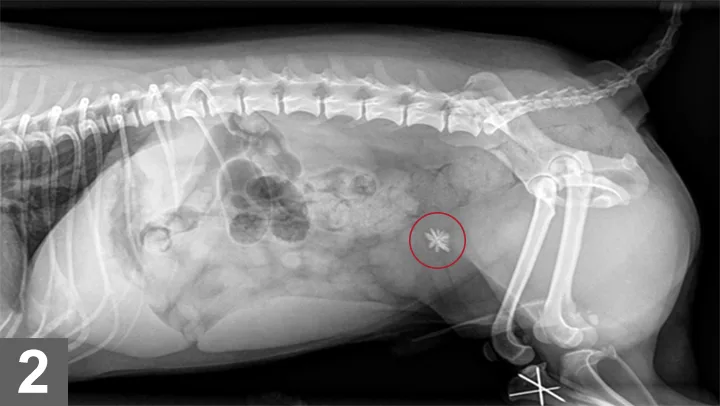

Silica-containing uroliths were rst reported in the United States in 1976 as associated with an increased use of plant-derived ingredients by the pet food industry and an increased availability of crystallographic techniques for urolith analysis. Silica-containing uroliths frequently, but not always, have a jack shape (Figure 1), although not all jack-shaped stones are silicates (ammonium urate, calcium oxalate, and struvite uroliths may also be jack-shaped). Silica-containing uroliths occur infrequently in dogs. Incidence ranged from 0.4%9.6%1-6 in several large retrospective studies at urolith analysis laboratories. Many of the reported silica-containing uroliths in the United States have occurred in German shepherd dogs, shih tzus, old English sheepdogs, and golden and Labrador retrievers. Most silica-containing uroliths are diagnosed in dogs 68 years of age, and males are affected more commonly than females (>9:1 M:F).2 In most dogs, numerous silica uroliths form, versus a solitary urolith. Silica-containing uroliths are radiographically opaque compared with surrounding soft tissue (Figure 2).

Figure 1

Multiple silicate uroliths removed from a dog. Photo courtesy of Dr. Howard Seim